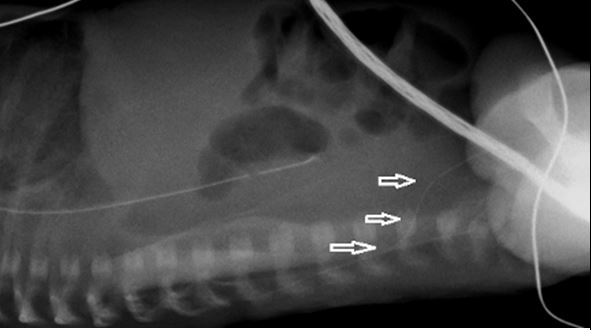

See illustrative x-rays below.

If there are any concerns that this complication has occurred, a lateral x-ray may show the line deviating posteriorly. If possible, seek advice from radiology about further imaging.

Such lines must not be used and the catheter should be removed. These lumbar veins are small, and extravasation of the infusate into the spinal canal may readily occur. This may result in permanent neurological injury and seizures.

These two x-rays show PICC lines that have entered the left lumbar vein. In both cases the line has not crossed the midline and lie to the left of the spine. Both X-rays show a kink in the route (arrow) although it is important to note that these kinks were not apparent on the initial x-rays and this feature cannot be relied upon |

This lateral x-ray shows a PICC line in the left lumbar vein taking a posteriorly deviated route (arrows). The correct route would show the line continuing to lie anterior to the spine. | |